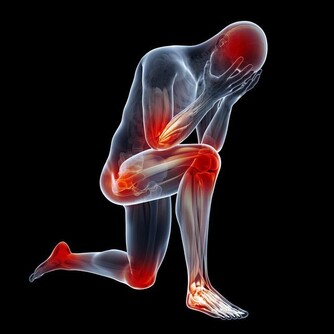

photos 其他預防方法:改善自我體質! 1. 益生菌:以Lactobacillus為主 (rhamnosus, casei and other species),確實數據上有: 降低感染的次數 已經感染時不舒服的天數 降低抗生素的使用 降低小朋友學校的缺席率(這竟然也有統計!?) 2. 口服或鼻用鋅的補充:10/15mg每天(不過每個研究吃的量差異很大),有機會減少感染天數和嚴重度。 3. 漱口:建議用水(日本是用生水因為含氯,但在台灣我還是建議開水好些)或含碘的漱口水漱口(市面上有專用配方)。一天4次,一次30秒以上,可以帶走/殺死致病的細菌或病毒,其實也算是切斷感染途徑。個人比較不喜歡酒精性的,殺菌性較不確定,且口感偏刺激些。理論上含氯的漱口水也可以,但相關研究較少。

以下是單就「預防感冒」而言是比較還好的: 1. 多運動:對感冒的發生率、嚴重度、發病天數相較之下較沒有明顯差異(不過多運動對長期心肺功能的改善和整體身體狀況還是很重要的,絕對不是叫大家不要運動。) 2. 維他命C:200-3000mg/天。對大部分人較沒明顯效果,官方多建議直接從五蔬果補充(但一樣,這是單就「預防感冒」,對身體健康而言還是要吃。) 3. 洗鼻子:對改善感冒症狀有效,預防角色還未知,需再研究。 4. 大蒜萃取物、人參等:預防角色還未知,需再研究。 以上方法若執行確實,能將被感染可能性降到最低,但不是杜絕。若真的身體有不適,還是要就近看醫生。